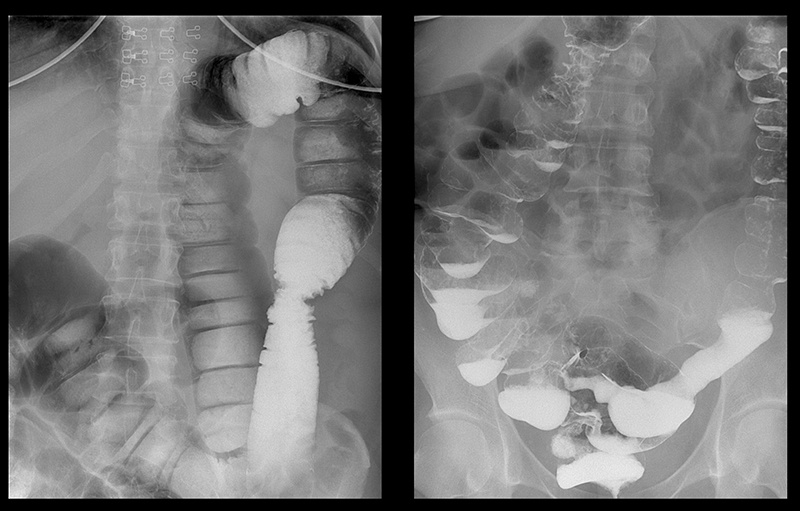

Przyjrzyj się zdjęciom narządów osób, które początkowo miały nieświeży oddech, zaparcia i zgagę, a ostatecznie otrzymały raport patologa.

„Rak jelita grubego u kobiety z częstymi zaparciami”

„USG kamieni kałowych w okrężnicy”

„Stopnie rozwoju raka odbytnicy rozwijającego się w ciągu 1–2 lat”